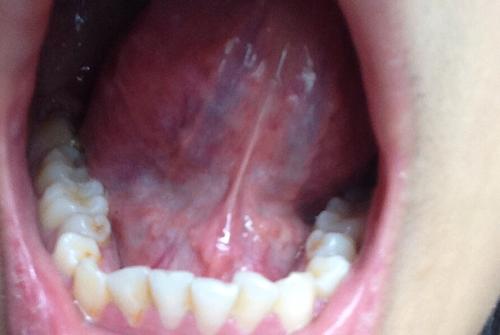

正常人舌头下面 肉芽,舌头下有小肉芽正常吗

儿子舌头底下有个小肉芽,早就有,但是最近几天长大了

舌头下有小肉芽正常吗

舌头下面有小肉芽

舌头下面长了个小肉芽

舌头下长肉芽图片说明

舌头底下长肉芽图片

小孩舌头下长肉芽图片

舌下系带肉芽图片